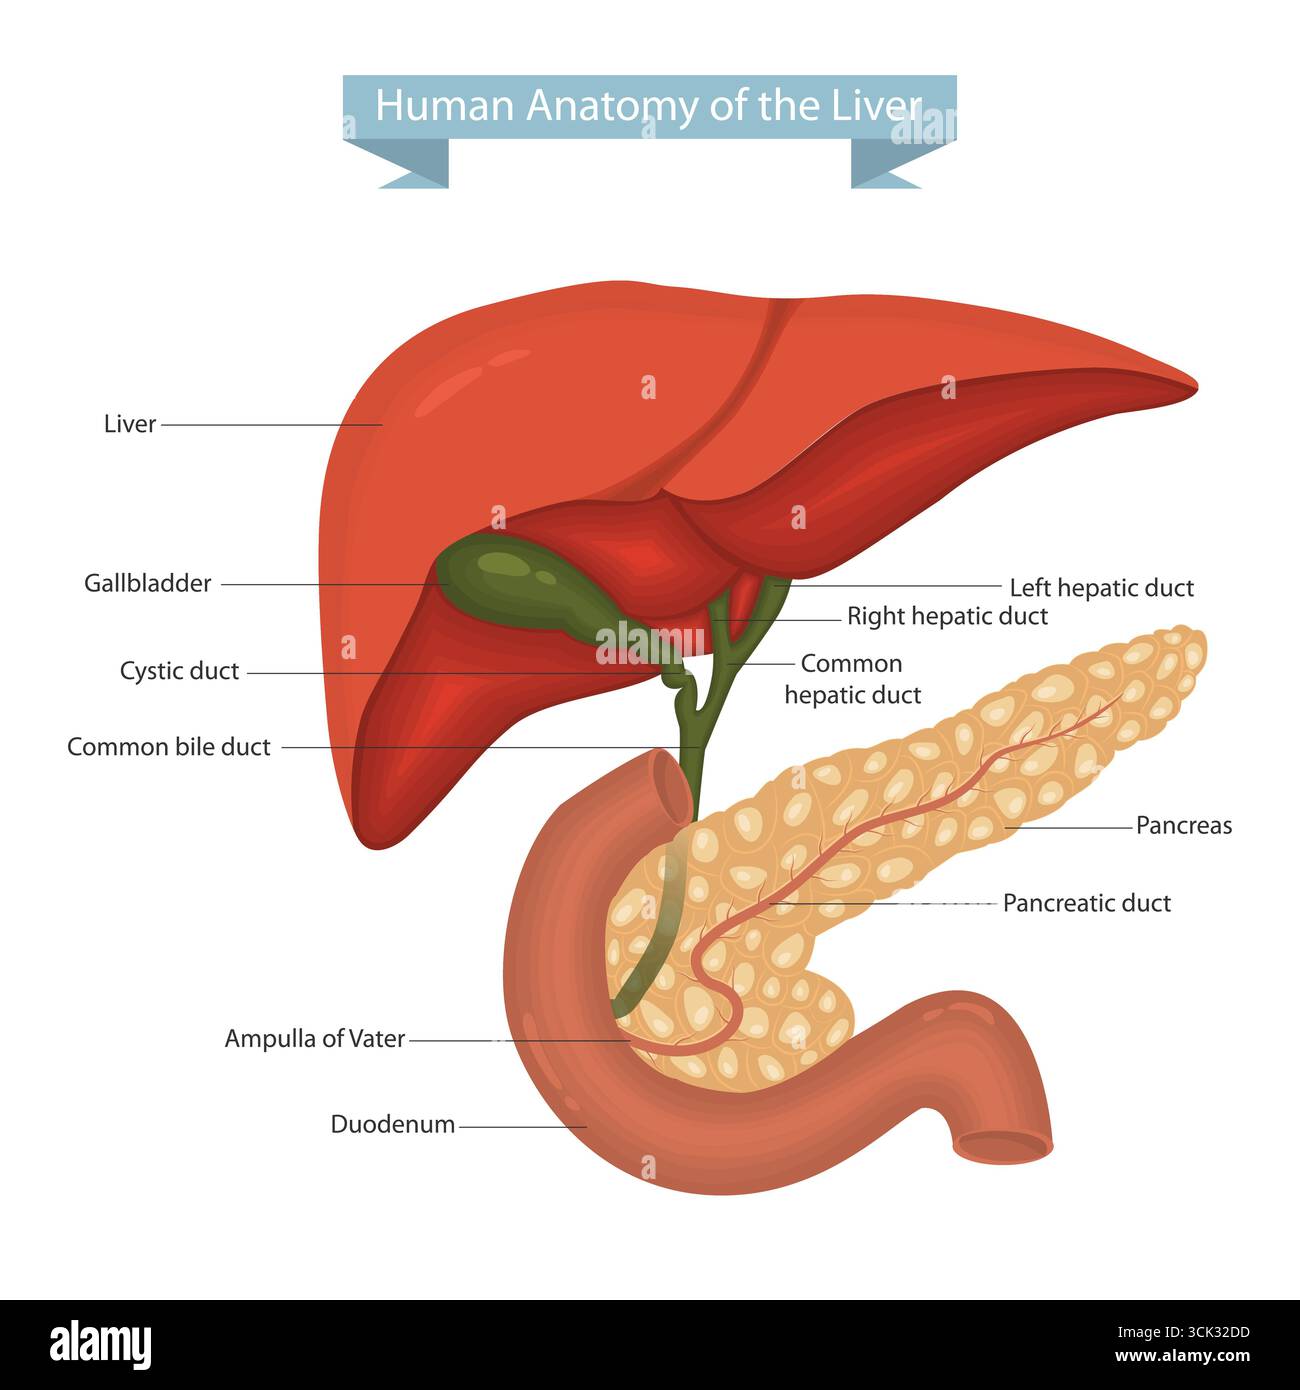

RF3CK32DD–Illustrazione vettoriale dettagliata dell'anatomia epatica umana con cistifellea, pancreas e duodeno. Anatomia epatica umana con pancreas e dotto biliare.